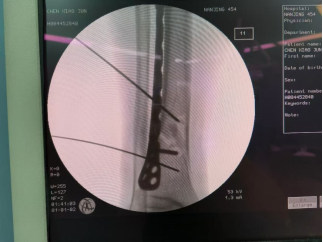

患者55岁男性,高处坠落致右侧小腿肿痛伴活动受限,影像检查显示胫腓骨下端骨折,行机器人辅助下复位及外固定架固定。术前外观连接机器人牵拉并透视调整机械臂,辅助复位安装外固定架六轴机器人辅助下腓骨穿针手术结束

1、踝关节粉碎性骨折本病例由中国中医科学院望京医院创伤一科提供(术者:CO接骨专家成主任)【基本资料】患者,男,42岁本病例胫骨远端骨折(右)。手术名称:右胫骨骨折闭合复位外固定架固定术【治疗前影像】【治疗中影像】【治疗后影像】【手术资料】【视频资料】